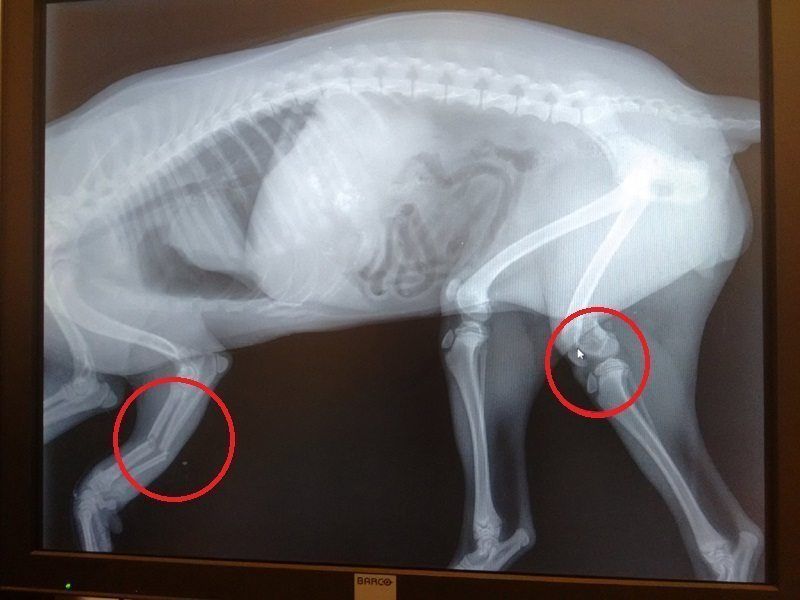

Η ακτινογραφία δείχνει τι υπέστη από το ξύλο και την πτώση.

Η ακτινογραφία δείχνει τι υπέστη από το ξύλο και την πτώση.